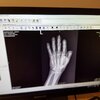

How does it feel? How is the mobility?So anyway, 10 weeks after my self amputation attempt, the pins are finally out of my finger.:dood:

XRays are cool...

So anyway, 10 weeks after my self amputation attempt, the pins are finally out of my finger.:dood: